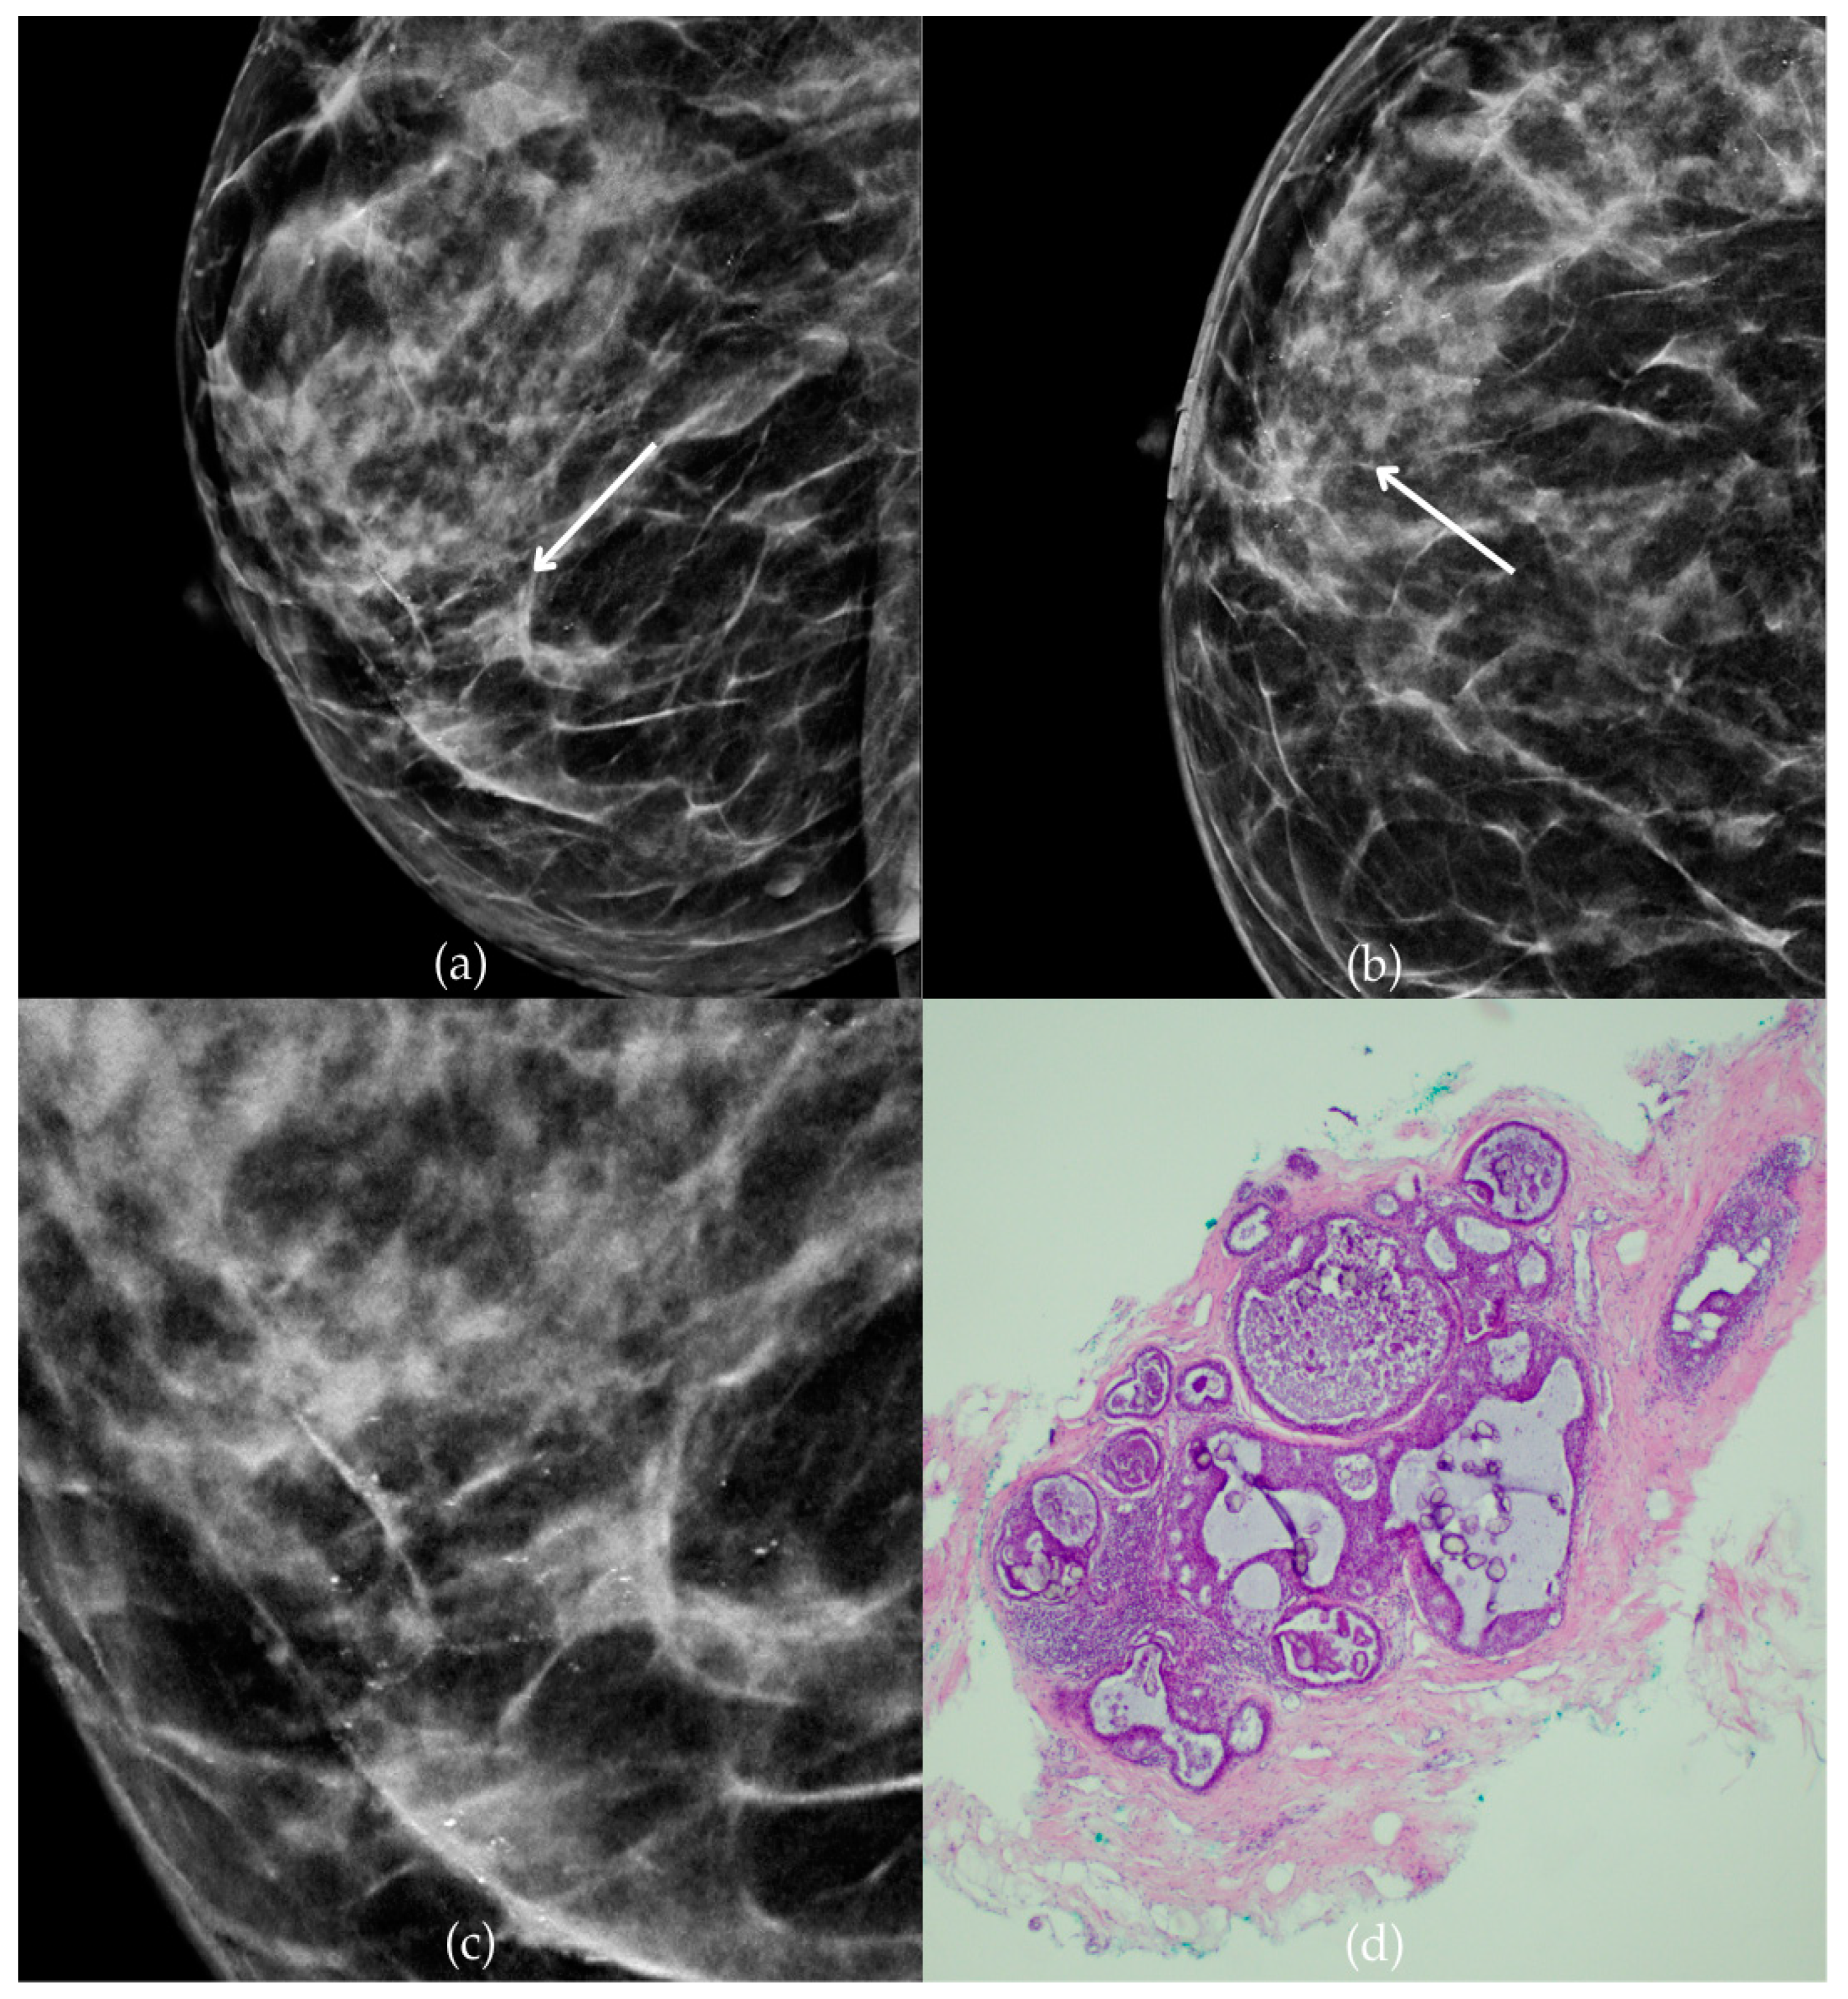

In Figure 2, mammographic and histopathological images illustrate the findings in a 51-year-old patient. The mammogram of the patient’s left breast shows architectural distortion with associated grouped amorphous calcifications over the 1 cm area in the upper outer quadrant, corresponding to a BI-RADS 4 finding. Tissue analysis obtained through biopsy confirmed morphological aspects of the DCIS (category B5a). Two years after the initial diagnosis, the most recent US follow-up was classified as BI-RADS 2, confirming benign findings.

Figure 2.

Ductal carcinoma in situ (DCIS). (a) Mediolateral oblique (MLO) view; (b) craniocaudal (CC) view of the left breast showing architectural distortion with associated grouped amorphous calcifications (marked with arrows) in the upper outer quadrant. (c) Magnified mammographic image of grouped amorphous calcifications within architectural distortion. (d) The histopathological image of the biopsy sample shows the characteristic features of DCIS with calcifications (marked with arrows) (HE staining; 100× magnification).